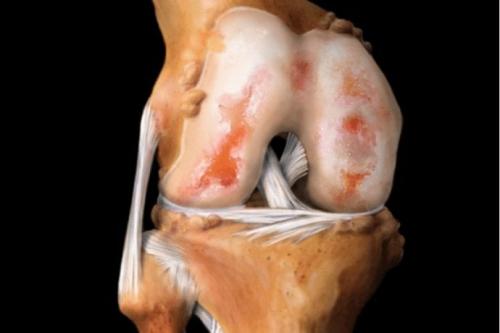

Вид на поражённую хрящевую поверхность.

Стадии артроза коленного сустава. Обратите внимание на сужение суставной щели.